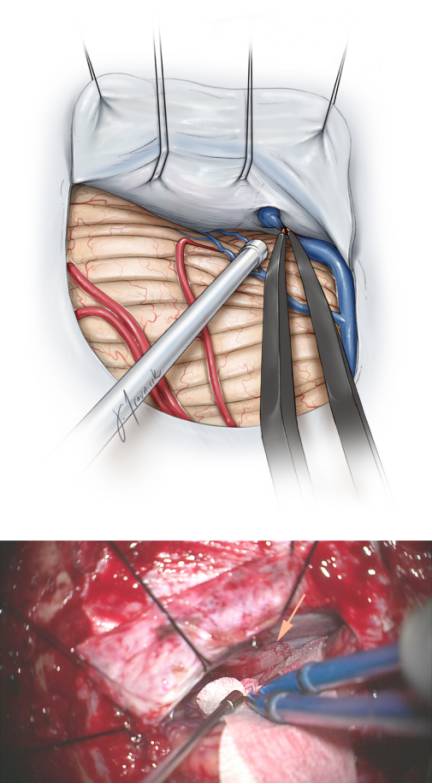

图5. 在小脑上入路的手术中,为了增加暴露有可能要切断中线旁引流静脉(上排)。图中展示的是肿瘤浸润的天幕(箭头)(下排)。

图6. 在切开天幕接近肿瘤的过程中,可通过锐性分离蛛网膜来充分暴露天幕游离缘的神经血管结构,早期的充分暴露能够避免在肿瘤切除过程中受到损伤。

充分锐性分离瘤旁的蛛网膜带会避免损伤滑车神经。